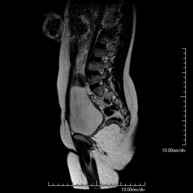

- RM Columna lumbar

Prueba diagnóstica no invasiva que consiste en la obtención de imágenes de alta definición anatómica de la lumbar y sacra, mediante el empleo de un campo electromagnético y ondas de radio (con un emisor y un receptor). No utiliza radiación ionizante. Indicaciones: traumatismos, ciática, hernias discales, tumores, infecciones.

- Columna

Prueba diagnóstica no invasiva que consiste en la obtención de imágenes de alta definición anatómica de la lumbar y sacra mediante el empleo de un campo electromagnético y ondas de radio (con un emisor y un receptor). No utiliza radiación ionizante. Indicaciones: traumatismos, ciática, hernias discales, tumores, infecciones.

- RM Sacro-cóccix

Prueba diagnóstica no invasiva que consiste en la obtención de imágenes de alta definición anatómica del sacro y cóccix mediante el empleo de un campo electromagnético y ondas de radio (con un emisor y un receptor). No utiliza radiación ionizante. Indicaciones: dolor sacrococcígeo, traumatismo.